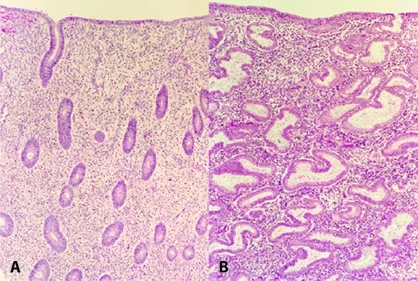

Endometrial Tissue Sections

- (A)proliferative phase.

- (B)secretory phases Of the menstrual cycle

The Proliferative Phase

After menstruation, when glandular and stromal growth begin. The epithelium lining the endometrial glands cells increase by mitoses. Endometrial thickness increases from 0.5 mm to 3.5–5 mm at the end of the proliferative phase.

The Secretory Phase

- After ovulation (around day 14)

- there is a period of endometrial glandular secretory activity.

- Endometrial thickness does not increase any further.

- The glands will become more tortuous.

- Spiral arteries will grow.